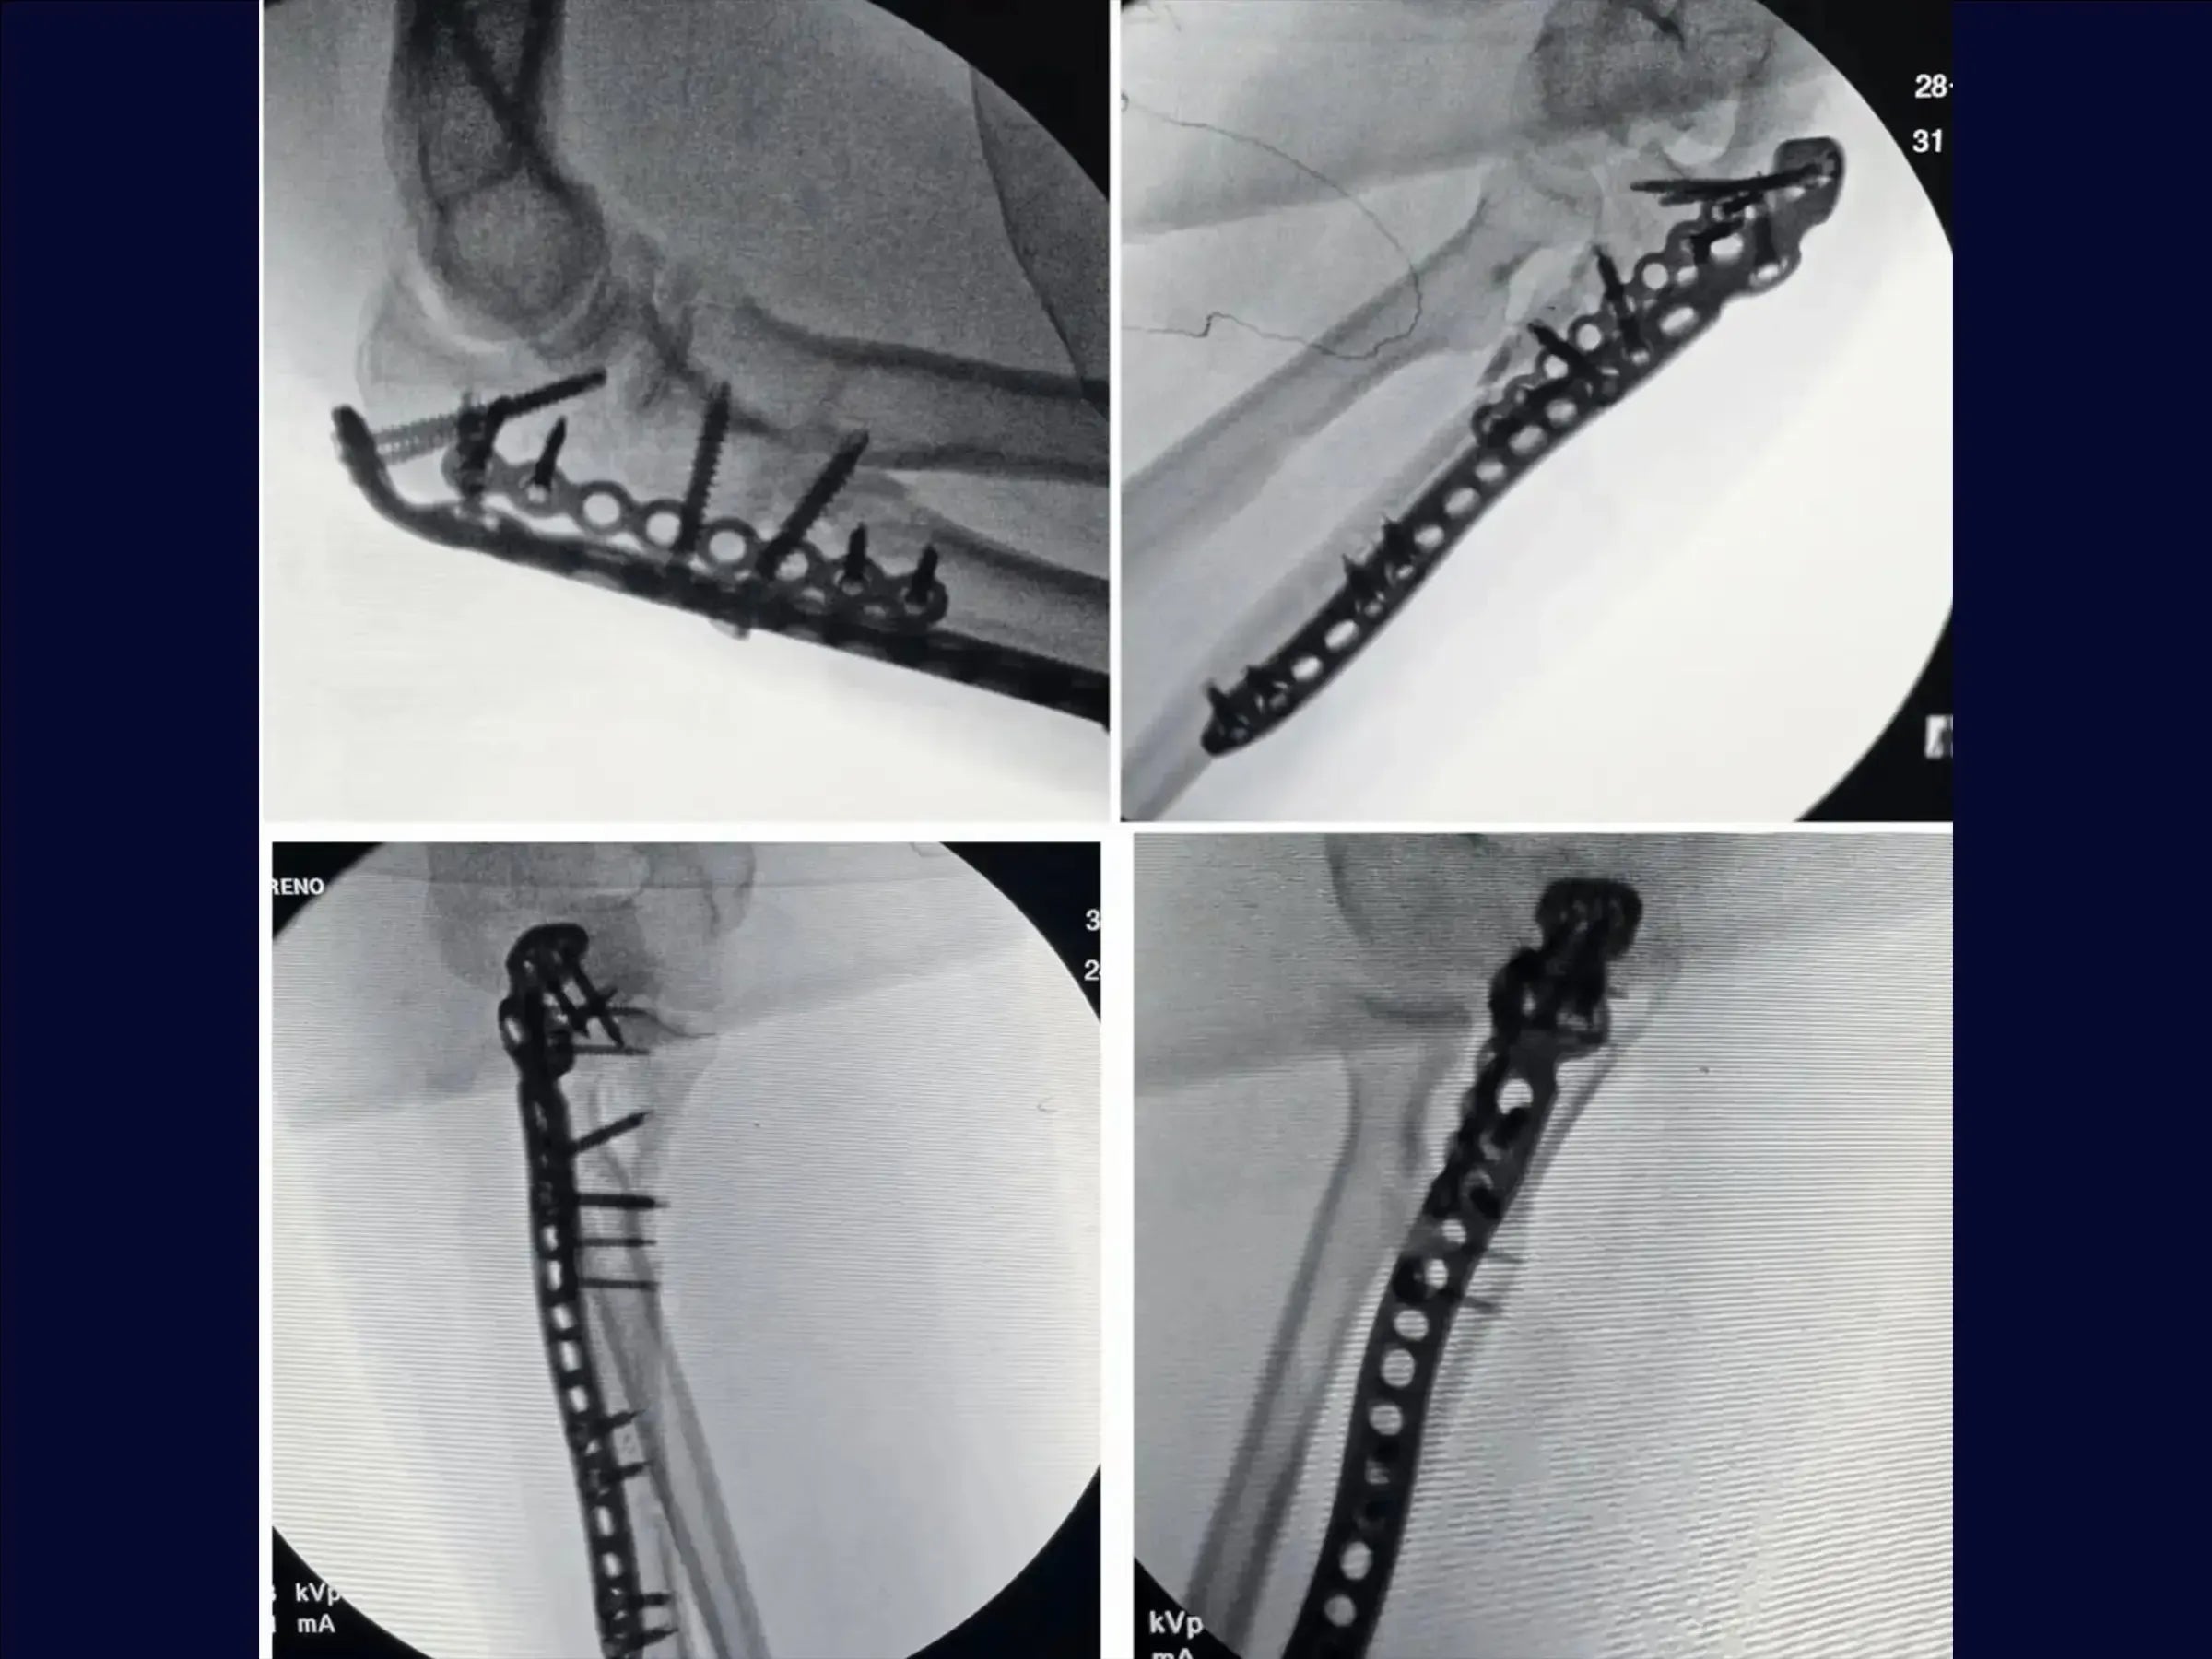

- Reduction of the Ulna: Fracture reduction with Kirschner wires.Lateral fragment fixation with a mini-fragment plate, enabling the use of a long plate on the olecranon.

- Finalization and Stabilization: Pull-out tying and definitive fixation with a long locked plate on the ulna metaphysis, ensuring joint stability.

- Closure and Final Result: Linear opening of the musculature, reconstructed fracture, and congruent joint. Well-distributed screws, with anatomical closure by layers.